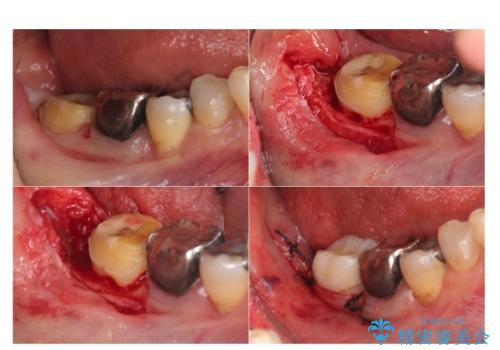

⑵歯周外科手術

今回は、歯周外科手術を行い、歯ぐきの厚みを薄くし、また、歯槽骨の高さも整えて、歯周環境を整えました。